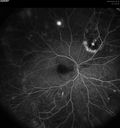

Self Sealed Retinal Arteriol Macroaneurysm469 viewsFA on presentation showed minimal to no active leakage. Also, there is a small cuff of blood around the MA which is favorable for closure

|